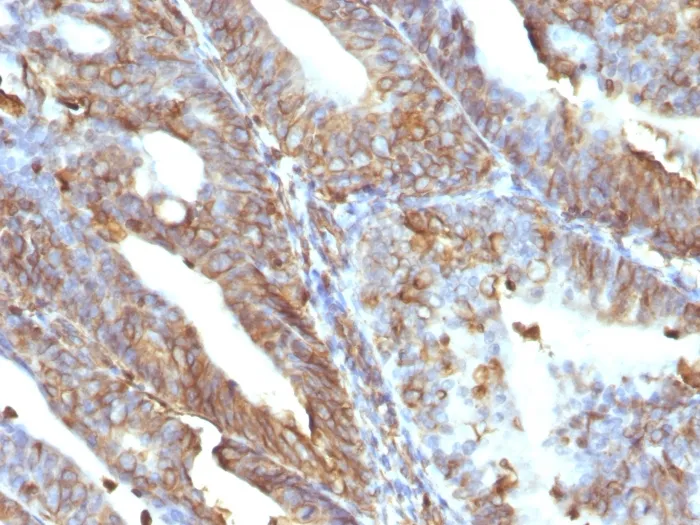

- Description: This MAb reacts with a 58 kDa protein identified as vimentin. It shows no cross-reaction with other closely related intermediate filament proteins (IFP's) such as desmin, keratin, neurofilament, and glial fibrillary acid protein. Anti-vimentin alone is of limited value as a diagnostic tool; however, when used in panels with other antibodies, it is useful for the sub-classification of a given tumor. Expression of vimentin, when used in conjunction with anti-keratin, is helpful when distinguishing melanomas from undifferentiated carcinomas and large cell lymphomas. All melanomas and Schwannomas react strongly with anti-vimentin. It labels a variety of mesenchymal cells, including melanocytes, lymphocytes, endothelial cells, and fibroblasts. Non-reactivity of anti-vimentin is often considered more useful than its positive reactivity, since there are a few tumors that do not contain vimentin, e. g. hepatoma and seminoma. Anti-vimentin is also useful as a tissue process control reagent. Primary antibodies are available purified, or with a selection of fluorescent CF® Dyes and other labels. CF® Dyes offer exceptional brightness and photostability. Note: Conjugates of blue fluorescent dyes like CF®405S and CF®405M are not recommended for detecting low abundance targets, because blue dyes have lower fluorescence and can give higher non-specific background than other dye colors.

- Applications: IHC, FFPE (verified) | WB (verified)

- Positive Control: U-87, Raji, Jurkat or HeLa cells. Sarcomas or Melanomas.